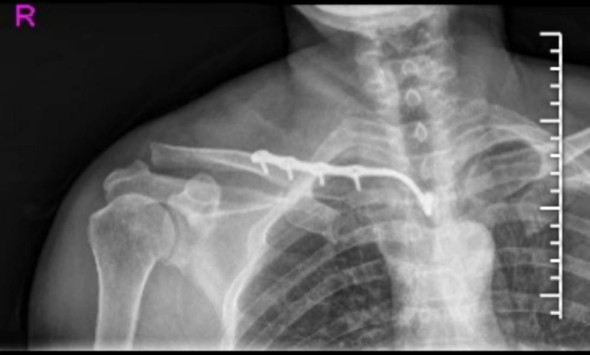

技术要点:锁骨骨折微创治疗之MIPO 锁骨骨折是临床常见损伤,其中约80%为锁骨中段骨折。锁骨骨折治疗方式和手术指征把握存在争议。对于14岁以内的未成年人基本可采取保守治疗,成年人保守和手术各有优劣。 成人锁骨骨折采用…

锁骨近端骨折,这样手术风险低! 锁骨近端解剖复杂,既往骨折多采用非手术治疗,预后不理想。近年来,治疗理念发生变化,手术治疗越来越多,本文整理了 胸锁钩钢板在锁骨近端骨折 的应用,供大家参考。 不说废话,先上病例 !! …